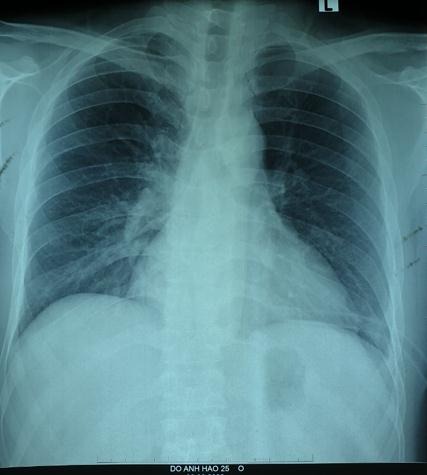

Tại đây, H. đã được chỉ định chụp X.quang ngực và được phát hiện có tình trạng có hình bóng hơi của ruột ở trên ngực trái (Ảnh 1). Bệnh nhân được hoàn thiện thêm các xét nghiệm cận lâm sàng và hội chẩn thêm các chuyên khoa, chụp cắt lớp khẳng định có thoát vị tạng bụng qua cơ hoành lên ngực trái. Sau đó, H. được chuyển tới Khoa Phẫu thuật Tiêu hóa - Gan mật tụy để tiến hành phẫu thuật.

- Chụp X.quang: Dấu hiệu mất liên tục vòm hoành, có hình ảnh mức nước hơi của quai ruột trong lồng ngực.